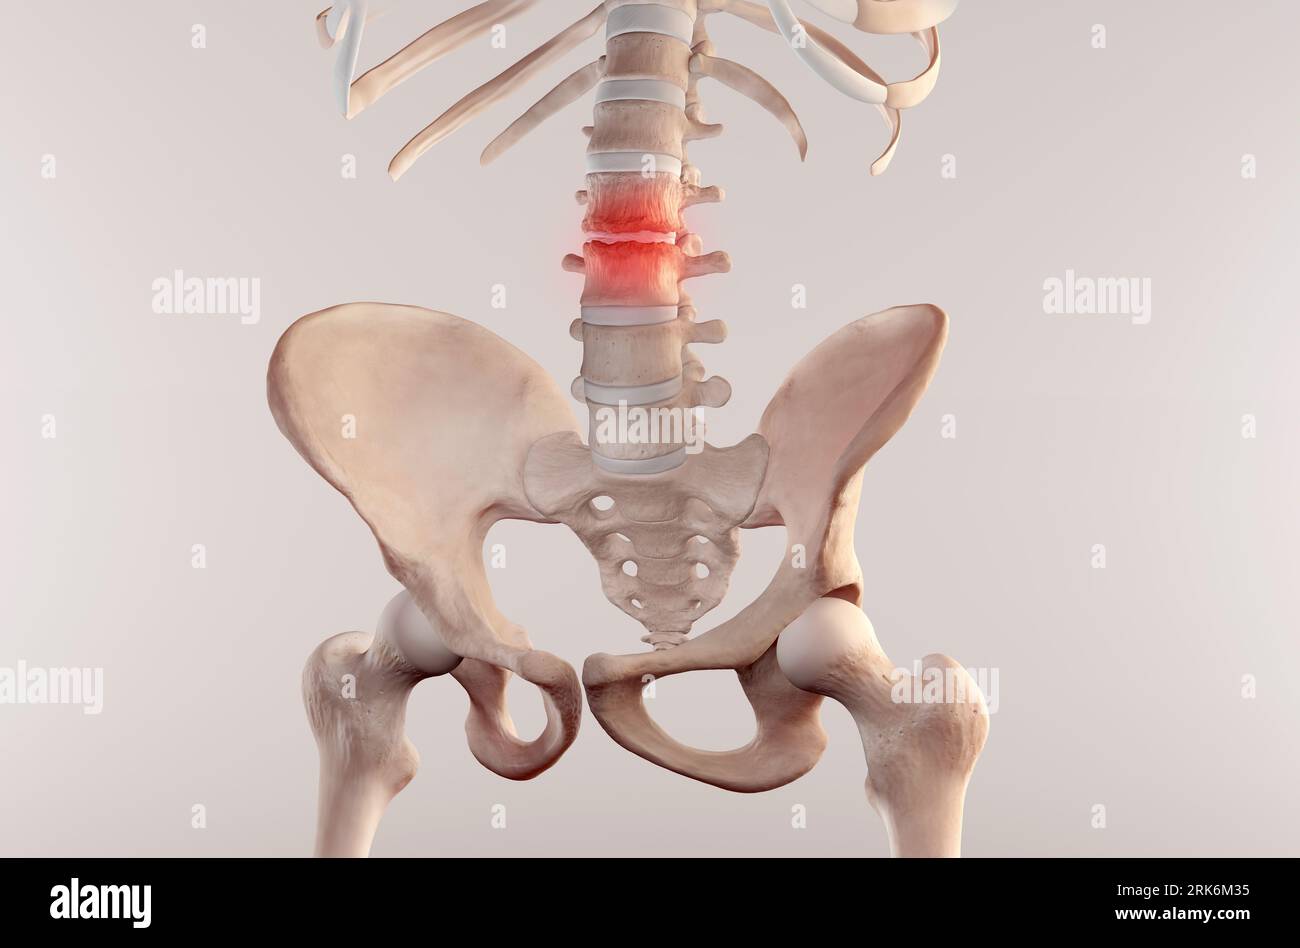

Anatomy of Human Spine. Lower back pain and human backache Stock Photohttps://www.alamy.com/image-license-details/?v=1https://www.alamy.com/anatomy-of-human-spine-lower-back-pain-and-human-backache-image562557721.html

Anatomy of Human Spine. Lower back pain and human backache Stock Photohttps://www.alamy.com/image-license-details/?v=1https://www.alamy.com/anatomy-of-human-spine-lower-back-pain-and-human-backache-image562557721.htmlRF2RK6M35–Anatomy of Human Spine. Lower back pain and human backache